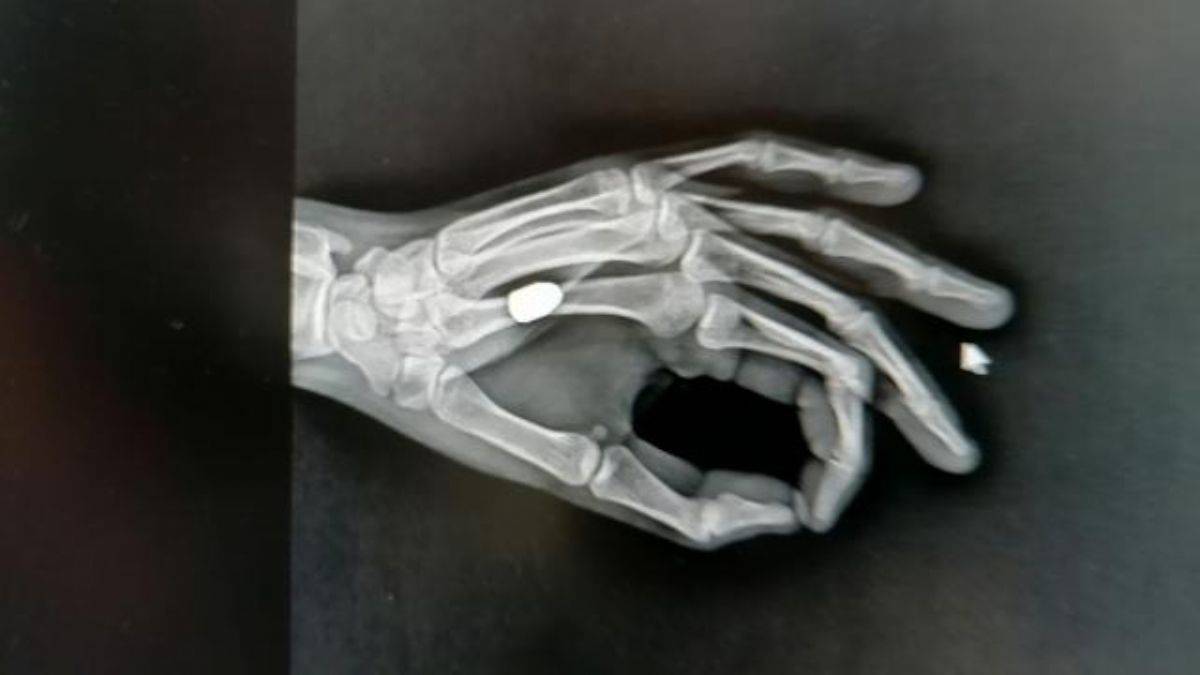

Tedaviye alınan İskender'e çekilen röntgende, avucuna yorgun merminin saplandığı tespit edildi. Mermi çekirdeği elinden ameliyatla alınan İskender, taburcu edildi. Polis ekipleri, olayla ilgili inceleme başlattı. Eline taş düştüğünü sandı, durumu hastaneye gidince öğrendi

Sürmene Devlet Hastanesi Başhekimi Osman Yoloğlu, röntgen filminde mermi tespit ettiklerini belirterek, "Elinde ağrı hissettiğini söyleyen hastamızın elinde de bir yarası vardı. Yaptığımız tetkikler sonrası elinde, mermi çekirdeği olduğunu tespit ettik. Hastamızı hemen ameliyata aldık ve elinden mermi çekirdeğini çıkarttık. Durumu, çok şükür iyi” diye konuştu.